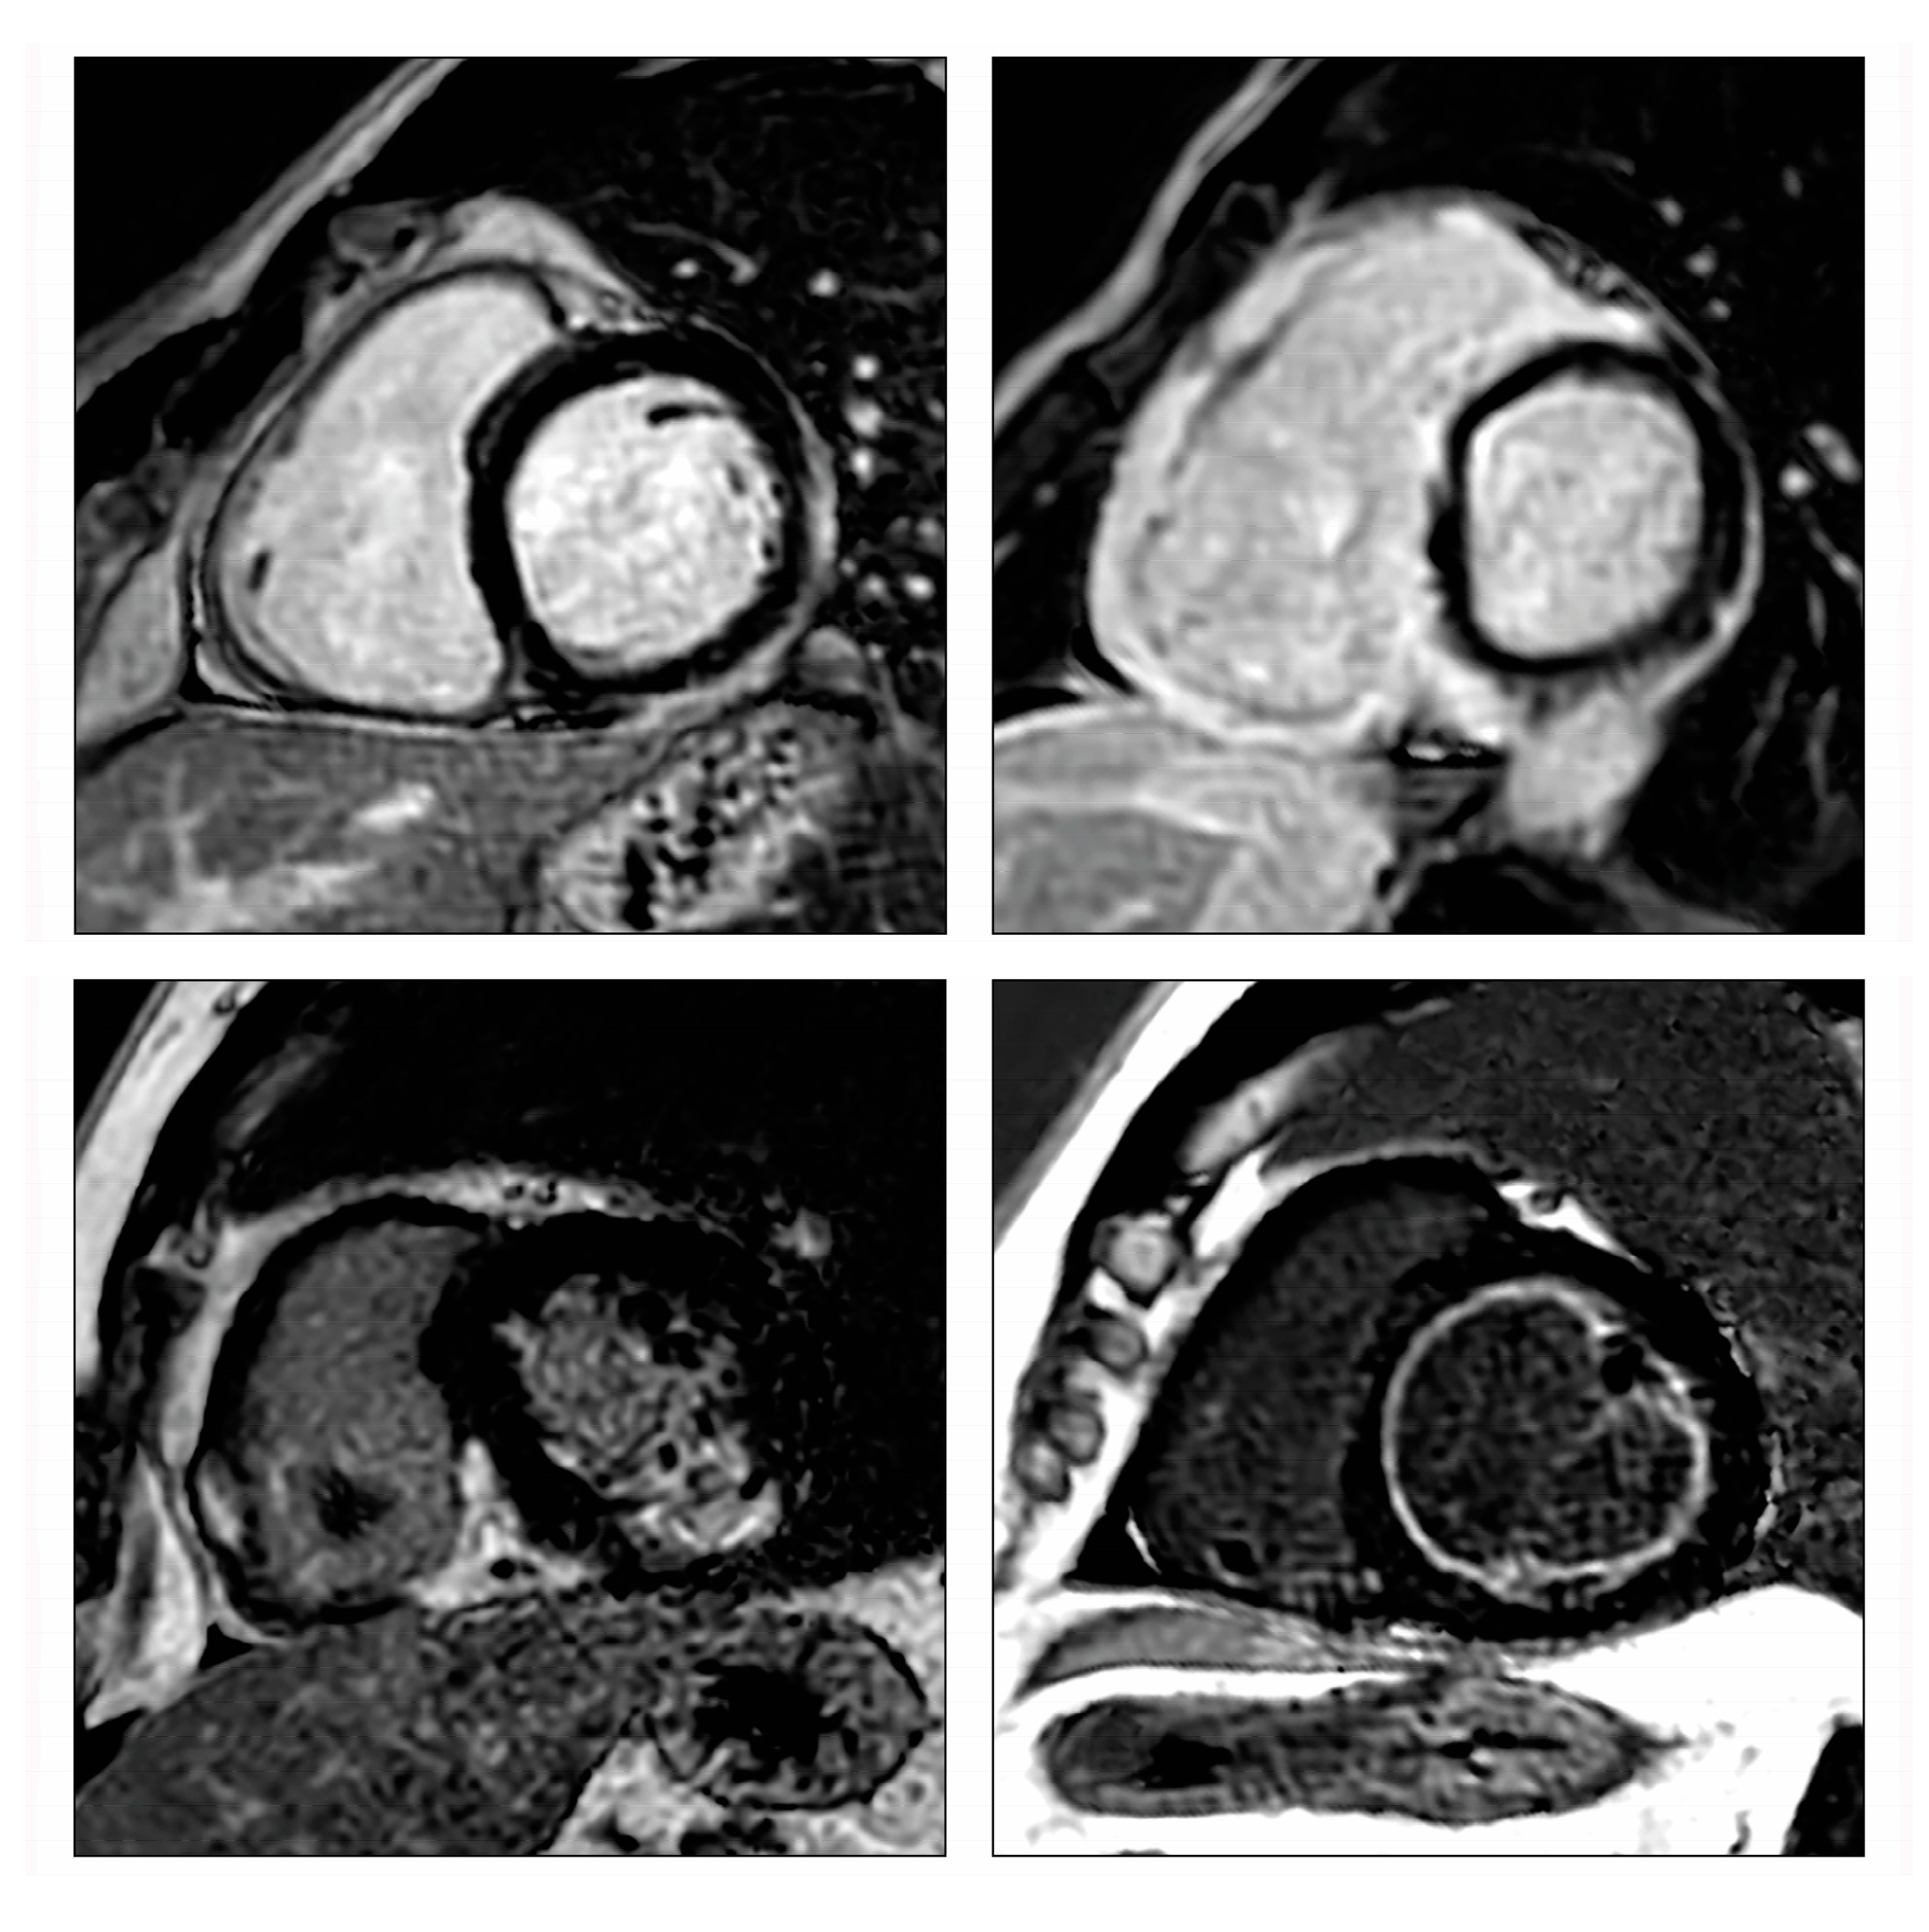

Cardiac magnetic resonance imaging (CMRI) has emerged as a powerful non-invasive diagnostic tool, mainly due to its multiparametric tissue characterization ability, and has been validated using EMB as a reference (Figure 3) [26,27,28]. CMRI is recommended in patients with clinically suspected myocarditis or in patients with chest pain, elevated troponin levels, and normal coronary arteries [26]. The ‘Updated Lake Louise Criteria’, a consensus guide enabling the CMRI-based diagnosis of myocarditis, focuses on the visualization of several hallmarks associated with myocardial inflammation: edema, hyperemia, capillary leak, myocardial necrosis, and fibrosis [26,29]. A high likelihood of myocarditis is assumed if “2 out of 2” diagnostic criteria are fulfilled: one positive T2-based criterion (T2-weighted imaging or T2 mapping) and one T1-based criterion (T1-mapping, extracellular volume, or late gadolinium enhancement (LGE)) [26,29]. CMRI conveys not only diagnostic but also prognostic information in patients with myocarditis [30,31].

Figure 3.

Characteristic late gadolinium enhancement (LGE) patterns in myocarditis. Characteristic late gadolinium enhancement (LGE) patterns in viral myocarditis (upper left) inferolateral subepicardial LGE), giant cell myocarditis (upper right) complex LGE involving both ventricles including the right ventricular insertion points), cardiac sarcoidosis (lower left) complex LGE involving both ventricles including the inferior right ventricular insertion point), and eosinophilic myocarditis (lower right) diffuse subendocardial LGE with high signal intensity). Re-used with permission from Polte et al. [27].